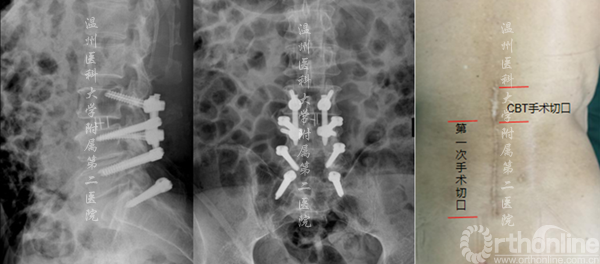

4-1Dynesys术后3年,腰3.4椎管狭窄。

术前X线资料

术中显露置钉的过程

术后X线资料(左侧)及术后切口对比(右侧)